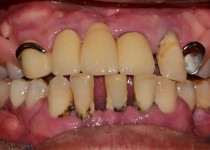

만 52세 전악 상악, 하악 전체 임플란트…

만 56세 상 하악 임플란트 증례